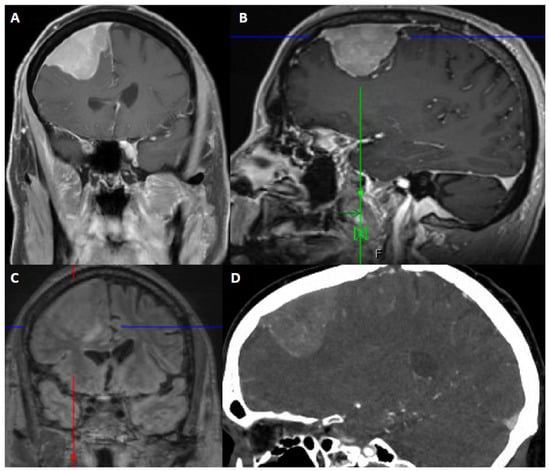

Figure 2. 67-year-old male presented with seizure and fall. After resection, pathology showed atypical meningioma, WHO grade 2. Molecular markers: TERT promoter wild type, positive for loss of chromosome 1p, 6, 14, 22, Y, segmental loss at 9p (haploinsufficiency of CDKN2A/B). Patient underwent right middle meningeal artery embolization preoperatively. (A) Coronal contrast-enhanced T1-weighted image shows an avidly contrast-enhancing dural-based mass, dural thickening and enhancement, a slightly multilobular border, and moderate mass effect. (B) Sagittal contrast-enhanced Magnetization Prepared-RApid Gradient Echo (MPRAGE) shows a reactive dural tail. (C) Coronal 3D fluid attenuated inversion recovery (FLAIR) sequence shows associated vasogenic edema. (D) Sagittal CTA of the head demonstrates internal vascularity.